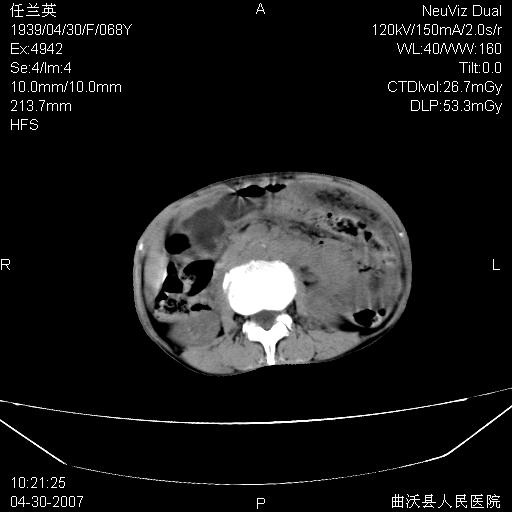

患者,女,68岁,感觉腹部憋涨发硬数天,查b超发现左盆腔有囊性肿物和少量腹水,行ct检查

支持:左侧卵巢恶性肿瘤伴网膜、腹膜 腹膜后(淋巴结)广泛转移。

难,腹膜后淋巴结转移。

支持卵巢恶性肿瘤腹膜.肠系膜.淋巴结转移,

支持卵巢恶性肿瘤腹膜.肠系膜.腹膜后淋巴结转移,

难的一见 典型 - 网膜饼  冰冻骨盆 可以当教学片了